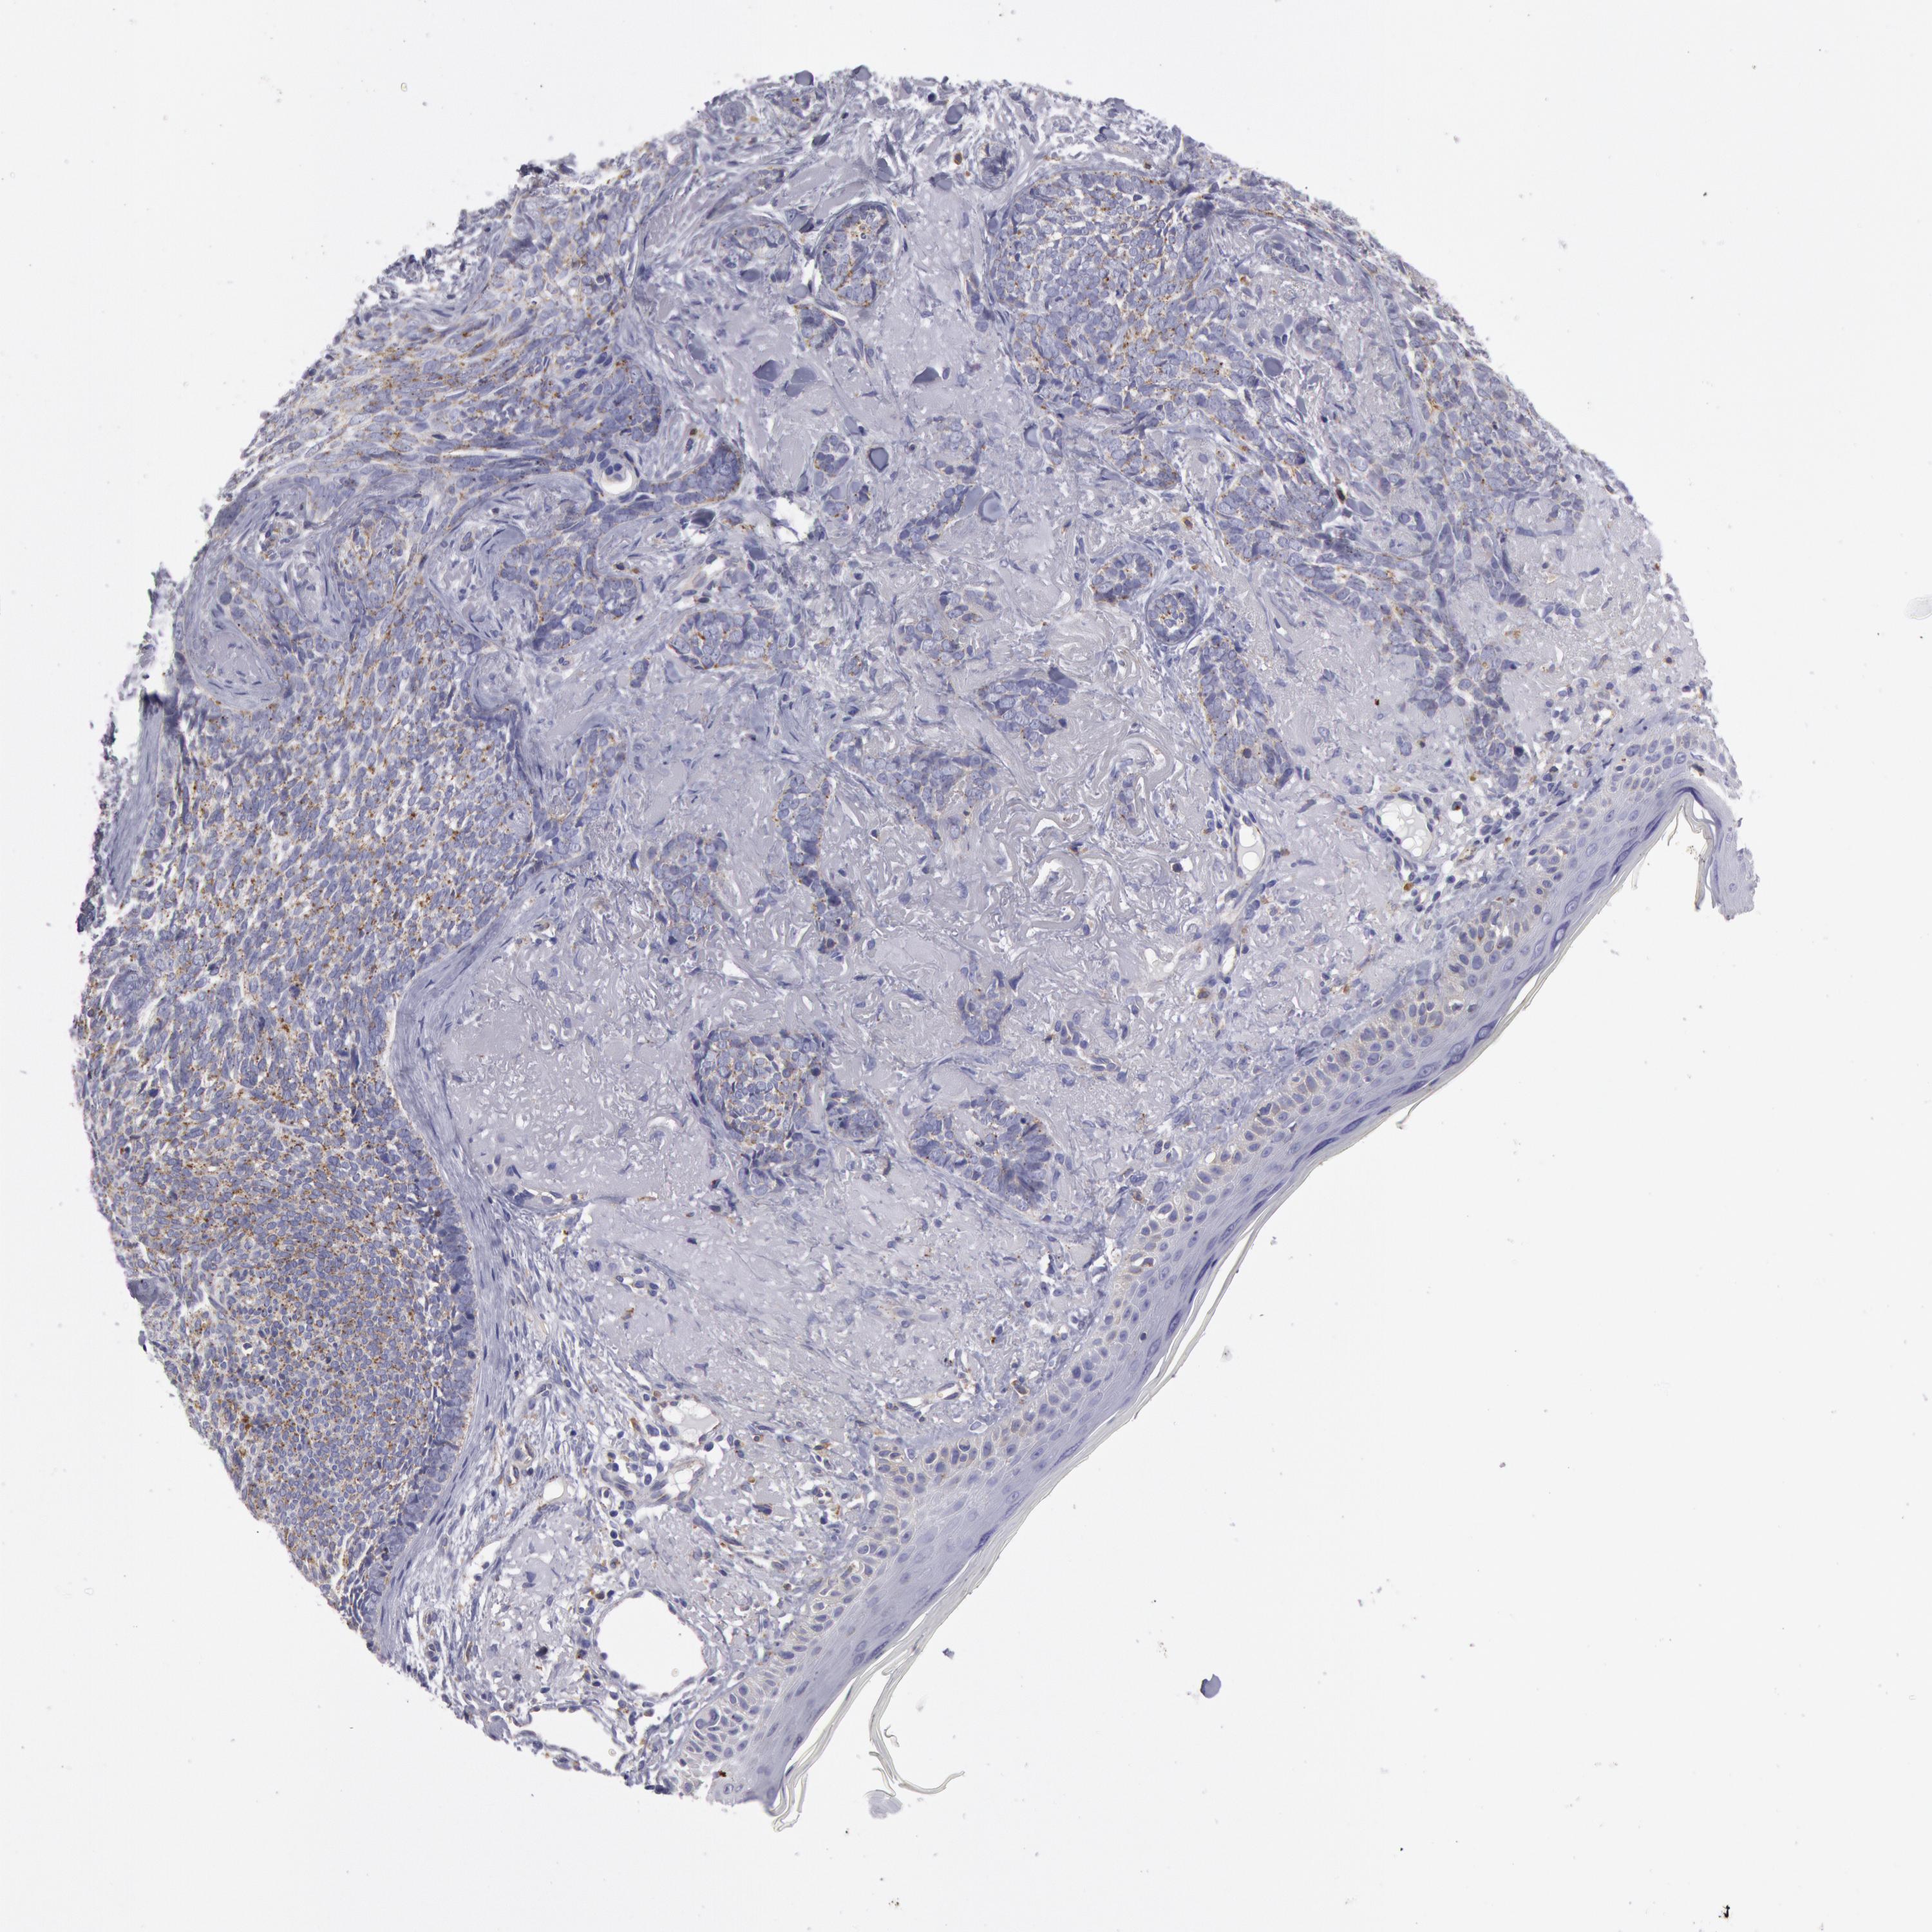

SKIN CANCER - Protein expressioni

A mouse-over function shows sample information and annotation data. Click on an image to view it in a full screen mode. Samples can be filtered based on level of antibody staining by selecting one or several of the following categories: high, medium, low and not detected. The assay and annotation is described here.

Each image is clickable and will lead to virtual microscopy that enables deeper exploration of all samples and also displays staining intensity scores, fraction scores and subcellular localization as well as patient and tissue information for each sample.

Antibody CAB007766

Staining

High

Medium

Low

Not detected

Intensity

Strong

Moderate

Weak

Negative

Quantity

>75%

75%-25%

<25%

None

Location

Nuclear

Cytoplasmic/membranous

Cytoplasmic/membranous,nuclear

Basal cell carcinoma

Squamous cell carcinoma, NOS

Squamous cell carcinoma, metastatic, NOS